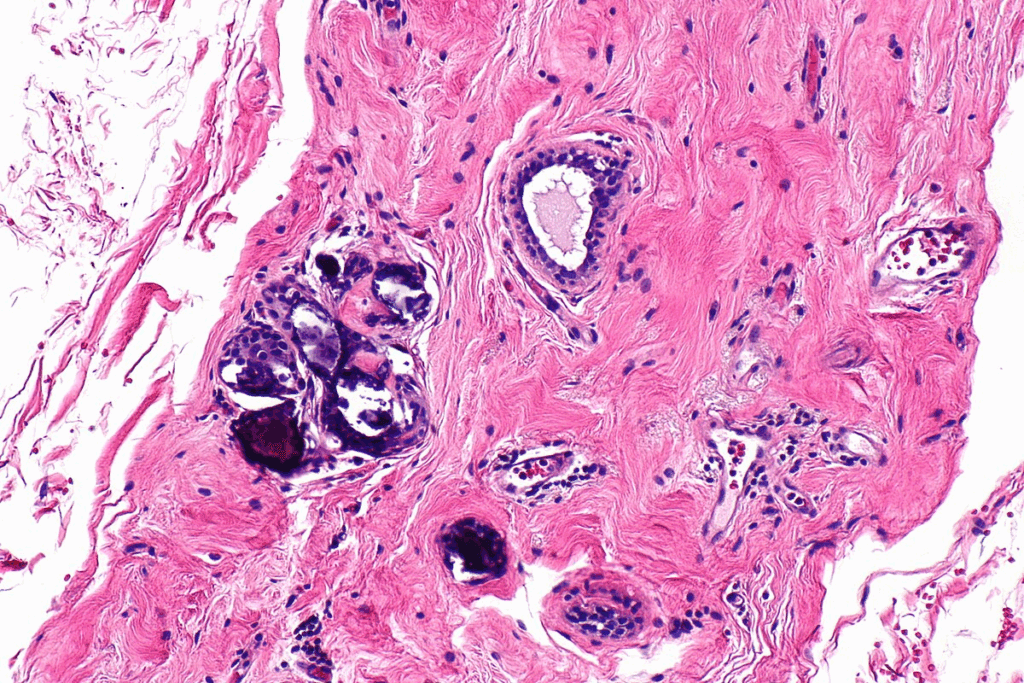

The Process of Atherosclerotic Calcification

Atherosclerotic calcification starts with plaque forming in the arterial intima. This process involves many cellular and molecular steps.

From Plaque Formation to Calcification

The journey to atherosclerotic calcification begins with endothelial dysfunction. This is when the inner lining of blood vessels gets damaged. This damage lets lipids get in and build up.

This buildup causes inflammation, drawing immune cells to the area. As it goes on, smooth muscle cells in the arterial wall get active. They help form a fibrous cap around the lipid core.

Over time, these smooth muscle cells start to act like bone-forming cells. They start depositing calcium, leading to calcification.

Progression from Microscopic to Macroscopic Deposits

The growth of arterial calcification from tiny deposits to large calcifications is complex. It involves many cellular and molecular steps.